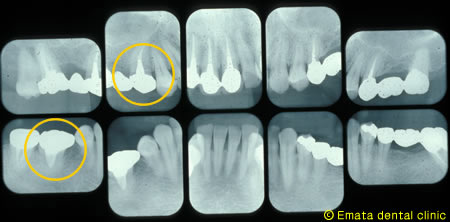

右上の虫歯が大きく、また右下の奥歯が根の病気が大きく抜歯になりました。 親知らずや内側に倒れた不必要になった歯があったので移植をおこないました。